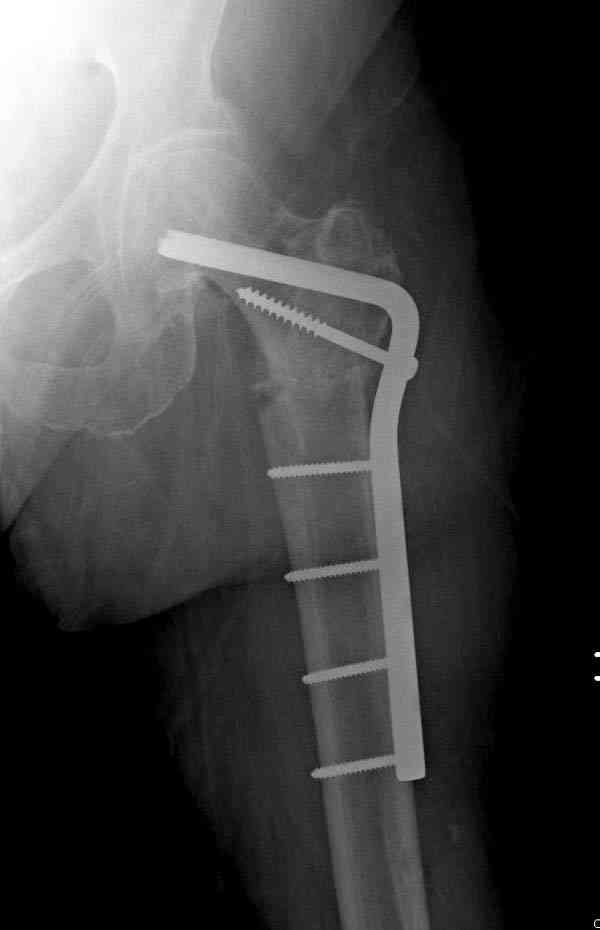

"2. Остеосинтез Г-образной пластиной 90 градусов с декортикацией и костной аутопластикой"

Г-образная пластина в 90 градусов неплохой вариант, но тогда за счет компрессии укорочение будет прогрессировать.

Не стали усложнять интрамедуллярным вариантом коррекции, легче контролировать коррекцию пластиной, поэтому сделали операцию 95 градусной Blade Plate, разогнув до 110 градусов.

Надеемся на успех, потому что до введения пластины дефект от импланта забили костной стружкой и удалось создать компрессию между отломками, максимальную для импланта (150 кило/паунд). Сделана дополнительная костная пластика и за счет измененного угла пластины устранено укорочение конечности.